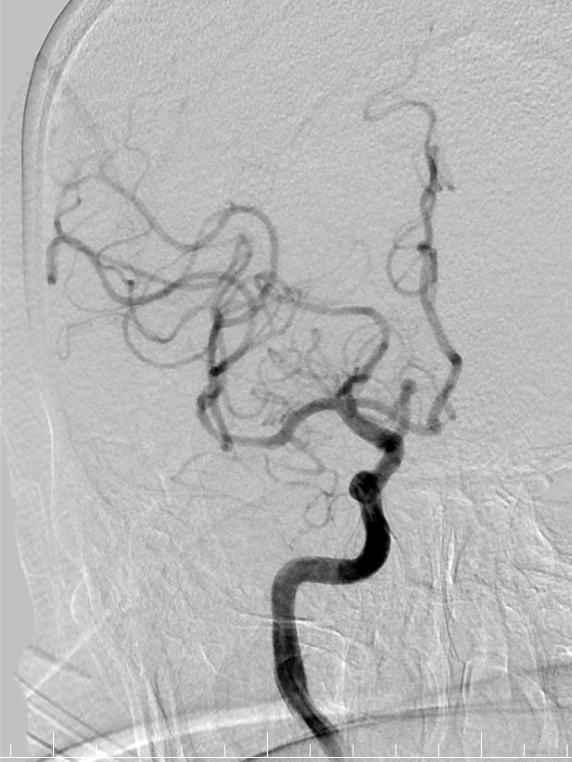

术后即刻影像。

动脉长鞘怎么置入有励可说|Locaste 088励楷长鞘及Tarvos微导丝在右侧大脑中动脉M2段取栓术中的应用_https://www.jmylbn.com_新闻资讯_第20张

动脉长鞘怎么置入有励可说|Locaste 088励楷长鞘及Tarvos微导丝在右侧大脑中动脉M2段取栓术中的应用_https://www.jmylbn.com_新闻资讯_第21张